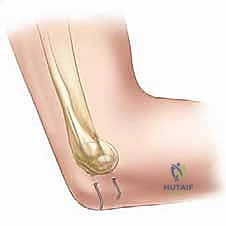

اللقيمة الوحشية (Lateral Condyle) هي الكتلة العظمية البارزة في الجزء الخارجي من النهاية السفلية لعظم العضد. تتكون هذه المنطقة الحيوية من عدة أجزاء أساسية:

- الرؤيس (Capitellum): وهو الجزء المفصلي المستدير الذي يتمفصل (يحتك بحركة دورانية) مع رأس عظم الكعبرة. هذا الجزء مغطى بغضروف أملس ويشكل جزءاً أساسياً من السطح المفصلي للكوع، مما يسمح بحركة دوران الساعد (مثل حركة استخدام مفك البراغي).

- جزء من الكردوس الجانبي (Lateral Metaphysis): وهو الجزء العظمي المتسع المجاور لصفيحة النمو.

- صفيحة النمو (Physis أو Epiphyseal Plate): وهي الأهم على الإطلاق. هي طبقة من الغضروف النشط خلوياً تقع بالقرب من نهايات العظام الطويلة عند الأطفال. هذه الصفيحة هي "المصنع" المسؤول عن إنتاج خلايا عظمية جديدة لزيادة طول العظم. في حالة كسر اللقيمة الوحشية، غالباً ما يمر خط الكسر كالسيف عبر هذه الصفيحة الحساسة.

الأربطة والعضلات المتصلة: قوة الشد المعاكسة

الجزء المكسور من اللقيمة الوحشية لا يظل ساكناً في مكانه كقطعة زجاج مكسورة، بل إنه يظل متصلاً بقوة بأنسجة رخوة وعضلات قوية:

1. عضلات باسطة الرسغ والأصابع (Extensor Musculature): تنشأ هذه العضلات من اللقيمة الوحشية. عند حدوث الكسر، تقوم هذه العضلات بشد القطعة المكسورة وسحبها للأسفل وللخلف.

2. مركب الرباط الجانبي الوحشي (Lateral Collateral Ligament Complex): يوفر استقراراً حاسماً للكوع.

بسبب هذه الانقباضات العضلية المستمرة، فإن كسر اللقيمة الوحشية يميل دائماً إلى "التباعد" و"الدوران" (Displacement and Rotation). هذا الشد العضلي هو السبب الرئيسي الذي يجعل علاج هذا الكسر بالجبس فقط أمراً مستحيلاً في معظم الحالات المتحركة، حيث تتطلب الحالة تثبيتاً ميكانيكياً (أسلاك معدنية) للتغلب على قوة العضلات. ومع ذلك، فإن هذه الاتصالات العضلية ضرورية جداً للحفاظ على إمداد الدم (Blood Supply) إلى القطعة المكسورة. الجراح الماهر يعرف كيف يرد الكسر دون تدمير هذه الأوعية الدموية الدقيقة.